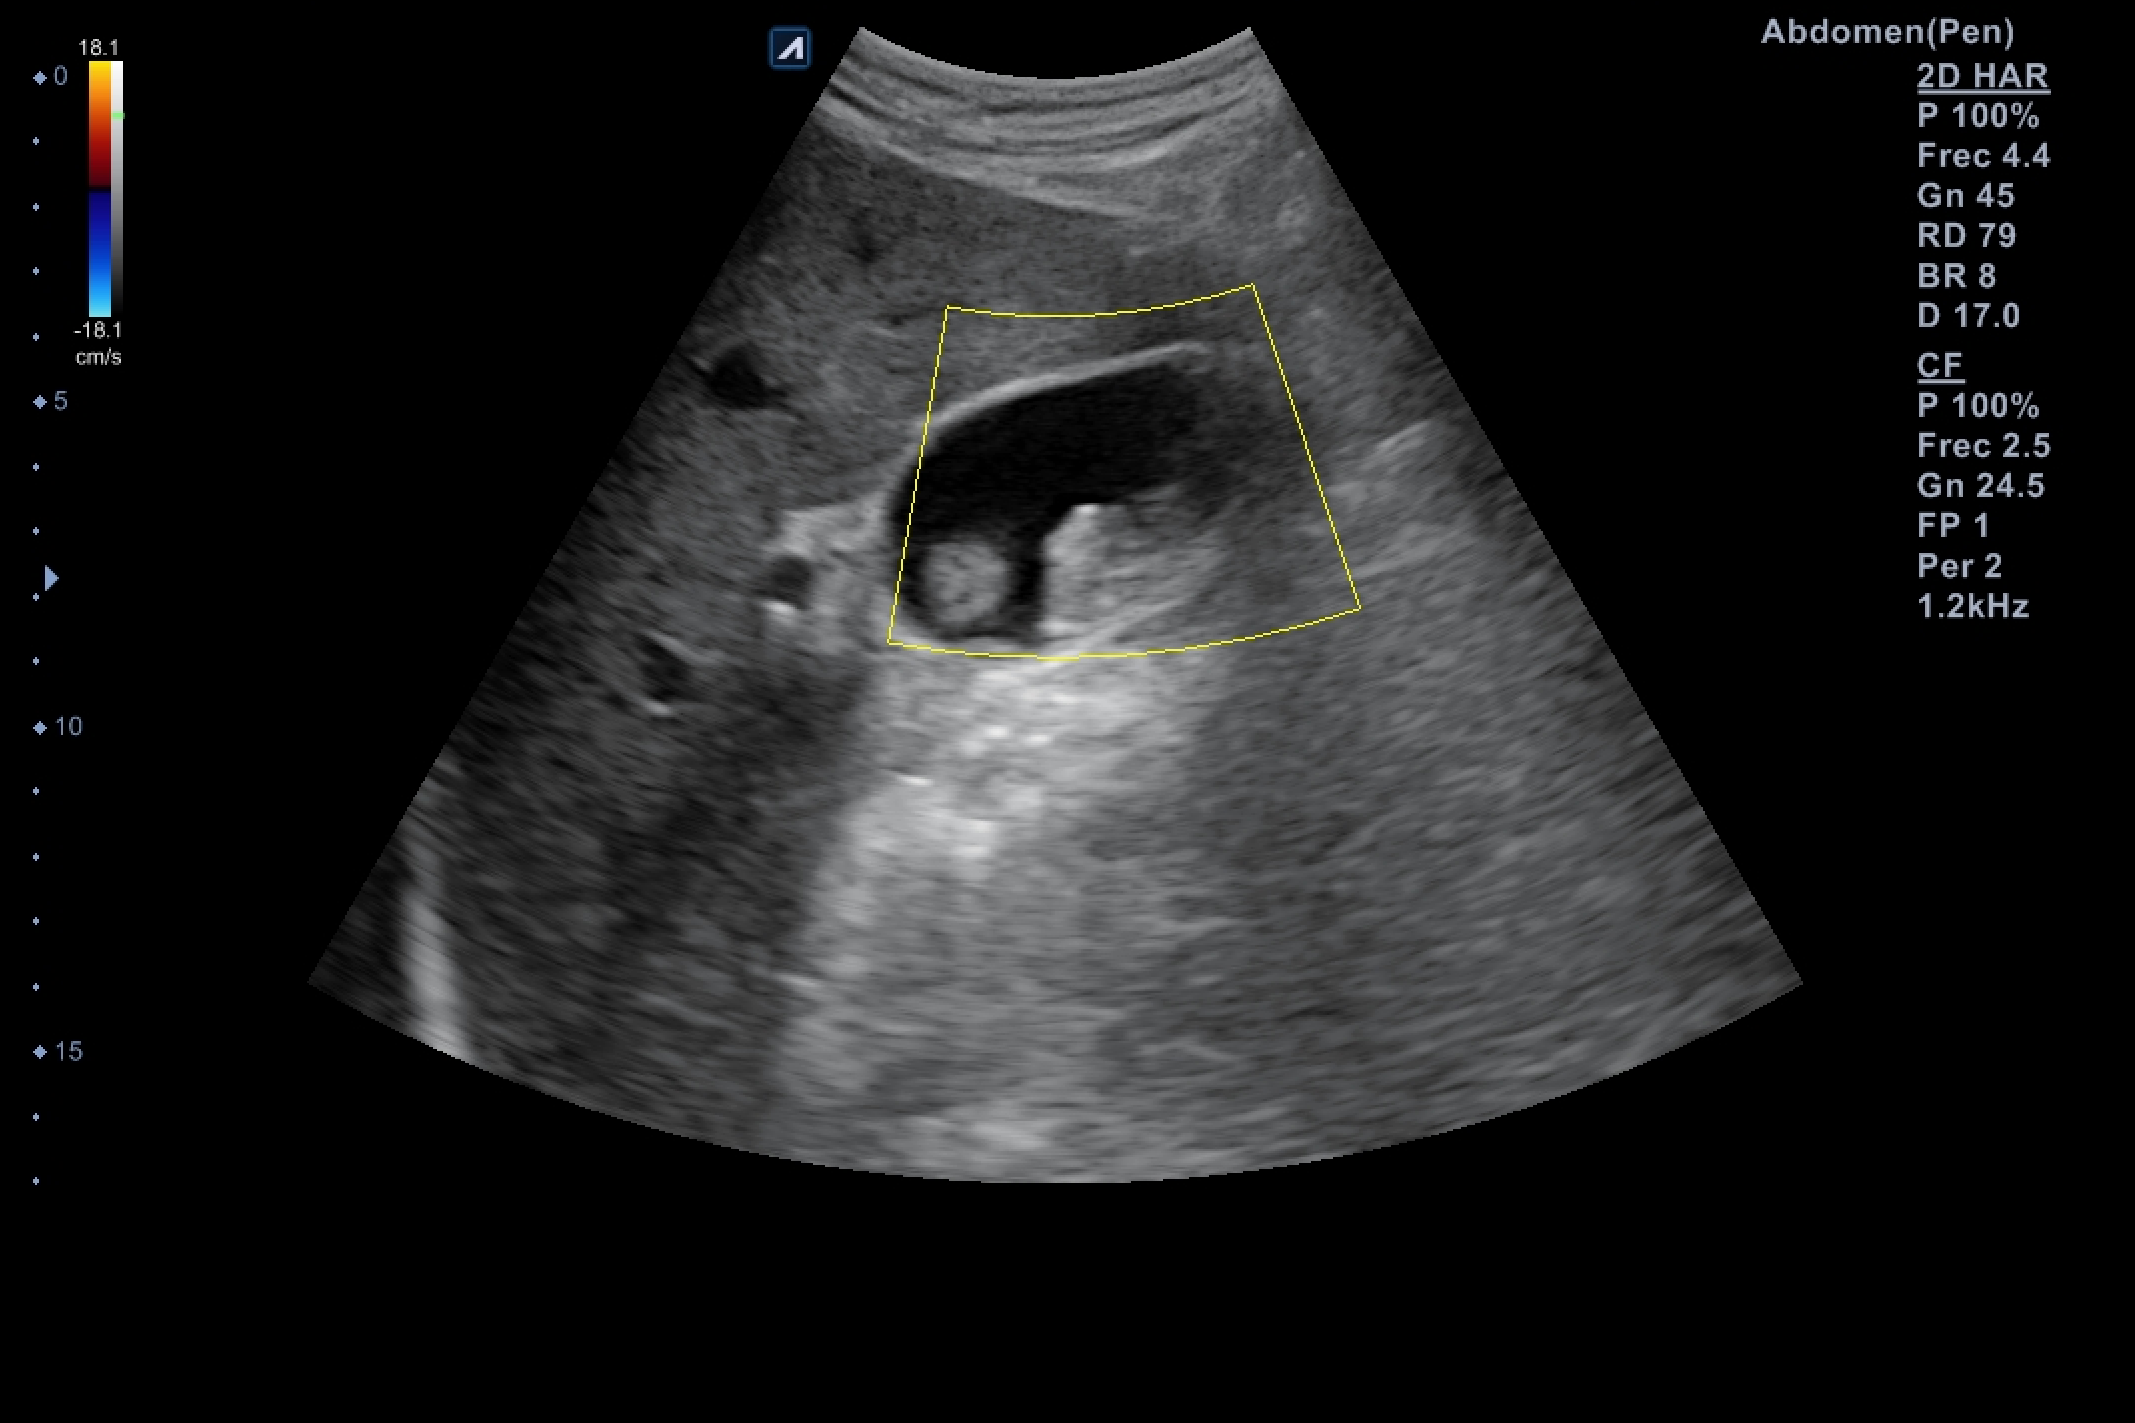

Ecografía abdominal dónde destaca vesícula biliar de pared fina (hasta 3,4 milímetros en su punto de mayor grosor) sin colecciones perivesiculares, que alberga en su interior imagen polilobulada sólida de efecto masa dependiente de su pared posterolateral e inferior que ocupa más de la mitad de la luz, sin captación de flujo Doppler, sugerente de polipoidea o tumoral, de unos 6 x 5 x 3 centímetros de dimensiones mayores.